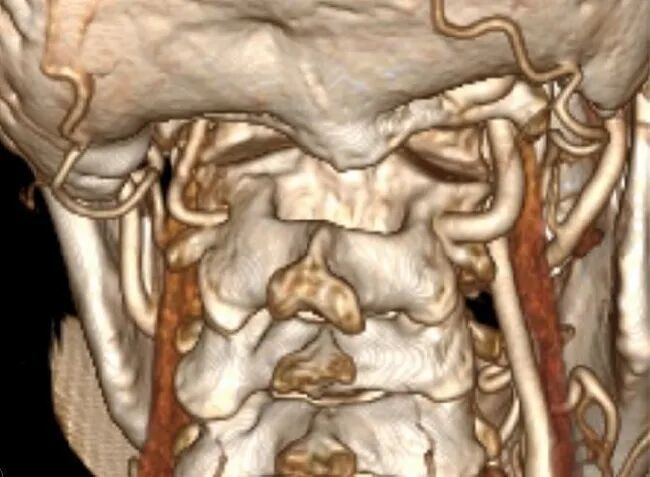

术前常规进行头颈部CTA扫描,应用计算机软件(推荐应用RadiAnt DICOM Viewer, Medixant Co.)对CTA Dicom数据进行三维重建详细观察颅颈交界区骨性结构畸形和椎动脉走行,制定手术方案,评估椎动脉损伤的风险。

椎动脉分型及手术策略

根据进行关节间操作时损伤椎动脉的危险程度,将椎动脉走行分为3种类型:低风险型,高风险型,禁忌型低风险型椎动脉:椎动脉走行不遮挡寰枢椎关节面,进行关节间操作损伤椎动脉的风险较低,此类患者通常没有寰枕融合,或寰枕融合不完全,寰椎保留横突孔结构,椎动脉受到寰椎横突孔的引导,走行路径正常,没有遮挡寰枢椎关节面(图9)。

对于此类椎动脉走行的患者,可以安全实施关节间撑开融合操作,手术中损伤椎动脉的风险较低。

高风险型椎动脉:椎动脉走行遮挡寰枢椎关节面,在进行寰枢椎关节间撑开操作过程中,损伤椎动脉的风险较高。并进一步分为Ⅰ型、Ⅱ型和Ⅲ型危险型椎动脉。

Ⅰ型高风险型椎动脉指患者一侧椎动脉走行异常,手术中损伤几率较高,但对侧椎动脉走行、管径正常,手术中损伤几率较低。手术中高风险椎动脉发生损伤,对侧低风险椎动脉可以代偿基底动脉血运,患者发生后循环缺血的风险较低(图10)。

Ⅱ型高风险型椎动脉,指两侧椎动脉皆为高风险型椎动脉,由于两侧椎动脉均走行异常,因此术中均存在较高损伤风险,如两侧椎动脉同时被损伤,患者可能发生后循环缺血(图11)。

Ⅲ型高风险型椎动脉,指患者一侧椎动脉为高风险性椎动脉,而对侧椎动脉退化或缺如,一旦高风险型椎动脉损伤,对侧椎动脉无法代偿基底动脉血供,可引发致命性基底动脉缺血(图12)

对于高风险型椎动脉,我们采用的治疗策略是将椎动脉向头侧抬起。显露寰枢椎关节后缘后,将关节间撑开器完全插入关节,如此,在旋转撑开器对关节间隙进行撑开的过程中,与椎动脉接触的是撑开器柱状的连接杆,避免对椎动脉造成卡压和切割,降低椎动脉损伤的风险(图13)。

禁忌型椎动脉:椎动脉穿行于寰枢椎关节面,进行寰枢椎关节间操作必然损伤椎动脉(图14)。这种椎动脉走行方式在关节间操作过程中尚无有效办法避开,因此是关节间撑开操作的禁忌证。